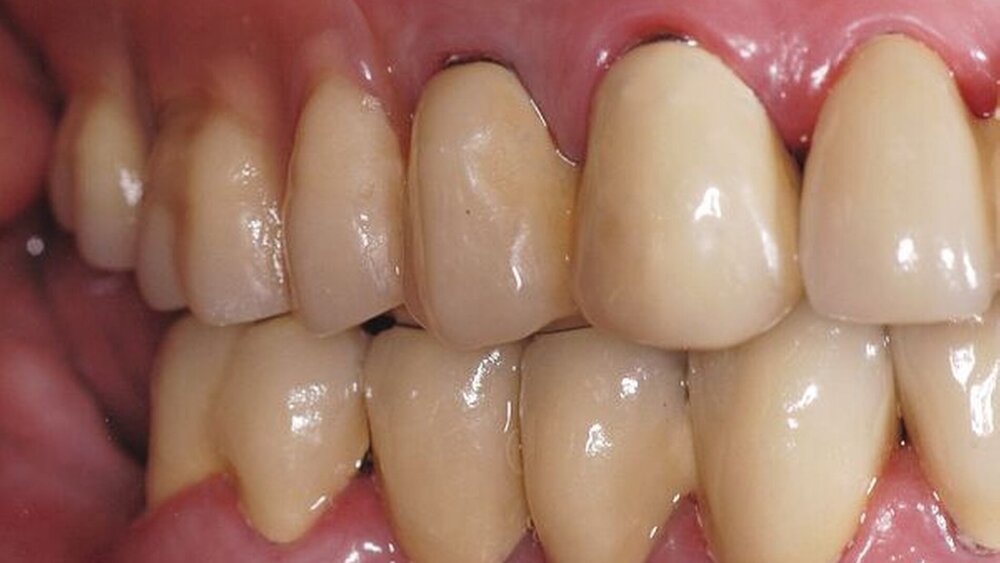

In der darauf folgenden Sitzung wurden alle Kronen und Brücken sowie die teleskopgetragene, partielle obere Prothese für einen Zeitraum von sieben Tagen zum Probetragen mittels eines Zements auf Zinkoxid-Eugenol-Basis eingegliedert. Dem Patienten sollte durch das Probetragen der Restaurationen beziehungsweise des angefertigten Zahnersatzes die Möglichkeit gegeben werden, sowohl die Funktion beim Essen und Sprechen als auch die Ästhetik im sozialen Umfeld zu testen. Ein erneutes Entnehmen der Restaurationen wäre – für den Fall notwendiger Korrekturen – somit ohne Weiteres möglich gewesen. Da der Patient sowohl die Funktion als auch die Ästhetik betreffend keine Änderungswünsche vorbrachte und auch keine neuerlichen Beschwerden aufgetreten waren, konnten die Restaurationen nach besagtem Tragezeitraum von sieben Tagen entnommen, gesäubert und mittels eines Glasionomerzements definitiv befestigt werden. Im Anschluss wurden erneut Situationsabformungen der Kiefer genommen und der Patient erhielt nach erneutem Checkbiss-Registrat, eine okklusal adjustierte Stabilisierungsschiene im Unterkiefer. Diese dient der Therapie der beschriebenen Bruxismusproblematik und gewährleistet einen langfristen Erfolg der eingegliederten prothetischen Restaurationen (Abbildungen 13a, 13b, 13c, 14, 15a, 15b, 15c).

Abschließend kann somit festgehalten werden, dass durch die gewählte Restaurationsform sowie durch die Art der technischen Umsetzung ein funktionell und ästhetisch sehr gutes Ergebnis erreicht werden konnte. Die Prognose des angefertigten Zahnersatzes ist bei entsprechender Compliance des Patienten sowie aufgrund der guten werkstofftechnischen Eigenschaften über einen Zeitraum von vielen Jahren als sehr gut einzustufen (Abbildungen 16a, 16b, 16c, 16d, 16e ).